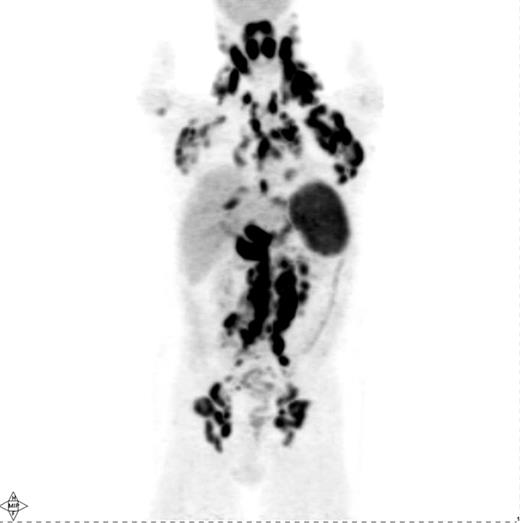

Pretreatment PET scan in a patient with Hodgkin lymphoma showing widespread cervical, axillary, mediastinal, hilar, abdominal and pelvic lymphadenopathy in addition to diffuse involvement of the spleen and focal liver involvement.

Several investigations have shown that PET is quite sensitive in detecting nodal and extranodal manifestations of HL prior to treatment (Figure 1 ).4,–14 Most of these studies have reported on mixtures of HL and NHL patients, although a few have specifically addressed the utility of PET for staging of HL.6,–13 In aggregate, these studies demonstrate that PET is able to detect an additional number of presumed HL sites compared with conventional staging methods, in particular CT and bone marrow biopsy (BMB). This results in a modification of disease stage (usually upstaging) in about 15–20% of patients with an impact on management in about 5–15%.4,–12 However, one drawback of these studies is that they did not provide histopathological verification of all or, at least most, of the additional PET findings not shown by conventional staging methods. Reports of up- or downstaging patients by PET were mostly based on theoretical considerations that assumed that the additional PET findings truly represented lymphoma.8,9,10,–14 Some studies used the disappearance of abnormal PET up-take following treatment as “proof” of the lymphomatous nature of these additional PET findings, a somewhat problematic approach considering that PET-positive benign entities such as fractures or inflammation may resolve with time irrespective of therapy.8,9,10,–14 Nevertheless, several conclusions can still be drawn, particularly based on the studies in which reported modifications of disease stage or management were based on PET findings verified by biopsy, additional imaging (e.g., MRI) or by posttreatment morphologic regression (by CT) of PET-positive lymph nodes presumed to be normal on pretherapy CT.4,–7,10 First, PET is able to detect focal or multifocal bone/bone marrow involvement in HL patients with negative iliac crest BMB, which could frequently be verified by guided biopsy of the PET-positive sites or by MRI.5,–7,12,15,–17 On the other hand, diffusely increased bone marrow uptake on PET may be due to reactive myeloid hyperplasia characteristic of some HL patients rather than lymphoma.16 In general, even focal/multifocal PET findings in the bone/marrow in the face of negative BMB should be confirmed whenever a change in treatment is contemplated based on PET. Second, PET alone is unreliable in detecting bone marrow involvement, particularly of limited degree (i.e., ≤10–20% of marrow space); an estimate of PET sensitivity for detecting marrow infiltration in HL based on a recently reported meta-analysis was 76% (95% CI 47–92).17,18 PET cannot, therefore, replace BMB in the staging of HL, at least based on currently available data. Third, PET and CT lead to concordant clinical stage in the vast majority of HL patients (60–80%).7,–13 However, several reports suggest that discordant findings occur in both directions: PET demonstrates abnormalities undetectable by CT resulting, on average, in altering stage in 15–20% of patients and CT shows abnormalities undetectable by PET with an impact of a similar magnitude (i.e., 10–20%) on stage assignment.7,–13 Abnormal findings seen only by PET with the potential for modifying disease stage or management include lymphomatous involvement of normal-sized lymph nodes by CT criteria (i.e., ≤ 1 cm in short axis), splenic and hepatic infiltration.4,–14 Although most studies show that PET-negative/CT-positive findings are less common than the reverse, it is clear from a number of investigations that PET alone cannot replace CT for pretreatment staging of HL.7,8,10,12 Rather, the modalities are complementary. Fourth, based on the complementary information from PET and CT, it appears likely that a PET/CT scan, which combines a PET and a CT scan in a single study, performed in the staging setting using i.v. contrast, will provide at least equal information to that provided by PET and a separately obtained i.v. contrast-enhanced CT (CECT) acquired using a dedicated CT scanner. The use of i.v. contrast when performing CT, regardless of whether it is performed as a separate study or as part of PET/CT, enables more accurate CT assessment of the liver and spleen. The adequacy of PET/CT performed under these conditions is supported by mostly retrospective or small trials showing that PET/CT performed even without i.v. contrast provides similar information to that provided by PET and a separately performed CECT.14,19 Thus, a pretreatment PET/CT with i.v. contrast may represent a reasonable choice of a modality providing an integrated functional/ anatomical assessment of HL with the added advantage of facilitating the interpretation of posttherapy PET or PET/ CT scans that are often obtained in patients with HL. However, pretreatment PET (PET/CT) is clearly not mandatory for staging and, while useful for a more reliable interpretation of posttherapy PET, is only fully justified outside of clinical trial setting if its results will alter patient management. Given the increasing reliance on systemic treatment with chemotherapy either alone or combined with radiation therapy (RT) depending on disease stage and certain risk factors (e.g., B-symptoms or bulky disease) PET is increasingly unlikely to result in a change in treatment approach if it demonstrates additional sites of disease or even alters the disease stage.8,10 In this context, it is noteworthy that Meyer et al demonstrated that in patients with nonbulky limited stage HL (clinical stage I and II A) there was no difference in overall survival between patients randomly assigned to receive treatment that includes RT or ABVD alone, making the latter a reasonable and often-utilized treatment option in such patients similar to the treatment utilized in patients with nonbulky advanced stage HL.20 Hence, PET upstaging of limited stage patients treated with ABVD alone would, in most instances, not have any impact on management. Interestingly, however, > 2 or 3 involved nodal regions are considered risk factors in limited stage HL according to the German Hodgkin Lymphoma Study Group (GHSG) and European Organization for Research and Treatment of Cancer (EORTC), respectively, and any extranodal disease is also considered a risk factor by the GHSG. According to treatment schemes recommended by these organizations, these risk factors warrant a more intensive treatment (i.e., a greater number of chemotherapy cycles combined with RT) in patients with nonbulky limited stage HL even without altering the disease stage.12,21 Based on such treatment schemes, PET detection of a greater number of nodal sites or extranodal disease would indeed result in a management change even without changing the disease stage.12